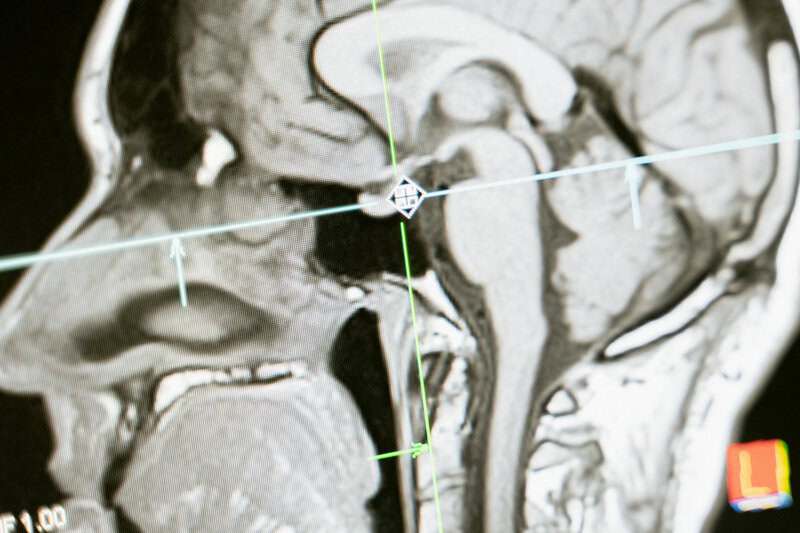

1. The Origin of Consciousness

A vivid illustration of the brain’s intricate neuron activity, highlighting the dynamic patterns of consciousness. | Photo by Karolina Grabowska www.kaboompics.com on Pexels

Despite significant progress in neuroscience, the emergence of consciousness—the subjective experience of awareness—remains elusive. Scientists have yet to pinpoint exactly how or why self-awareness arises from neural activity, leading to ongoing debates and varied theories. Some suggest emergent complexity, while others propose panpsychism, the idea that consciousness is a fundamental and ubiquitous feature of the physical world. (livescience.com)